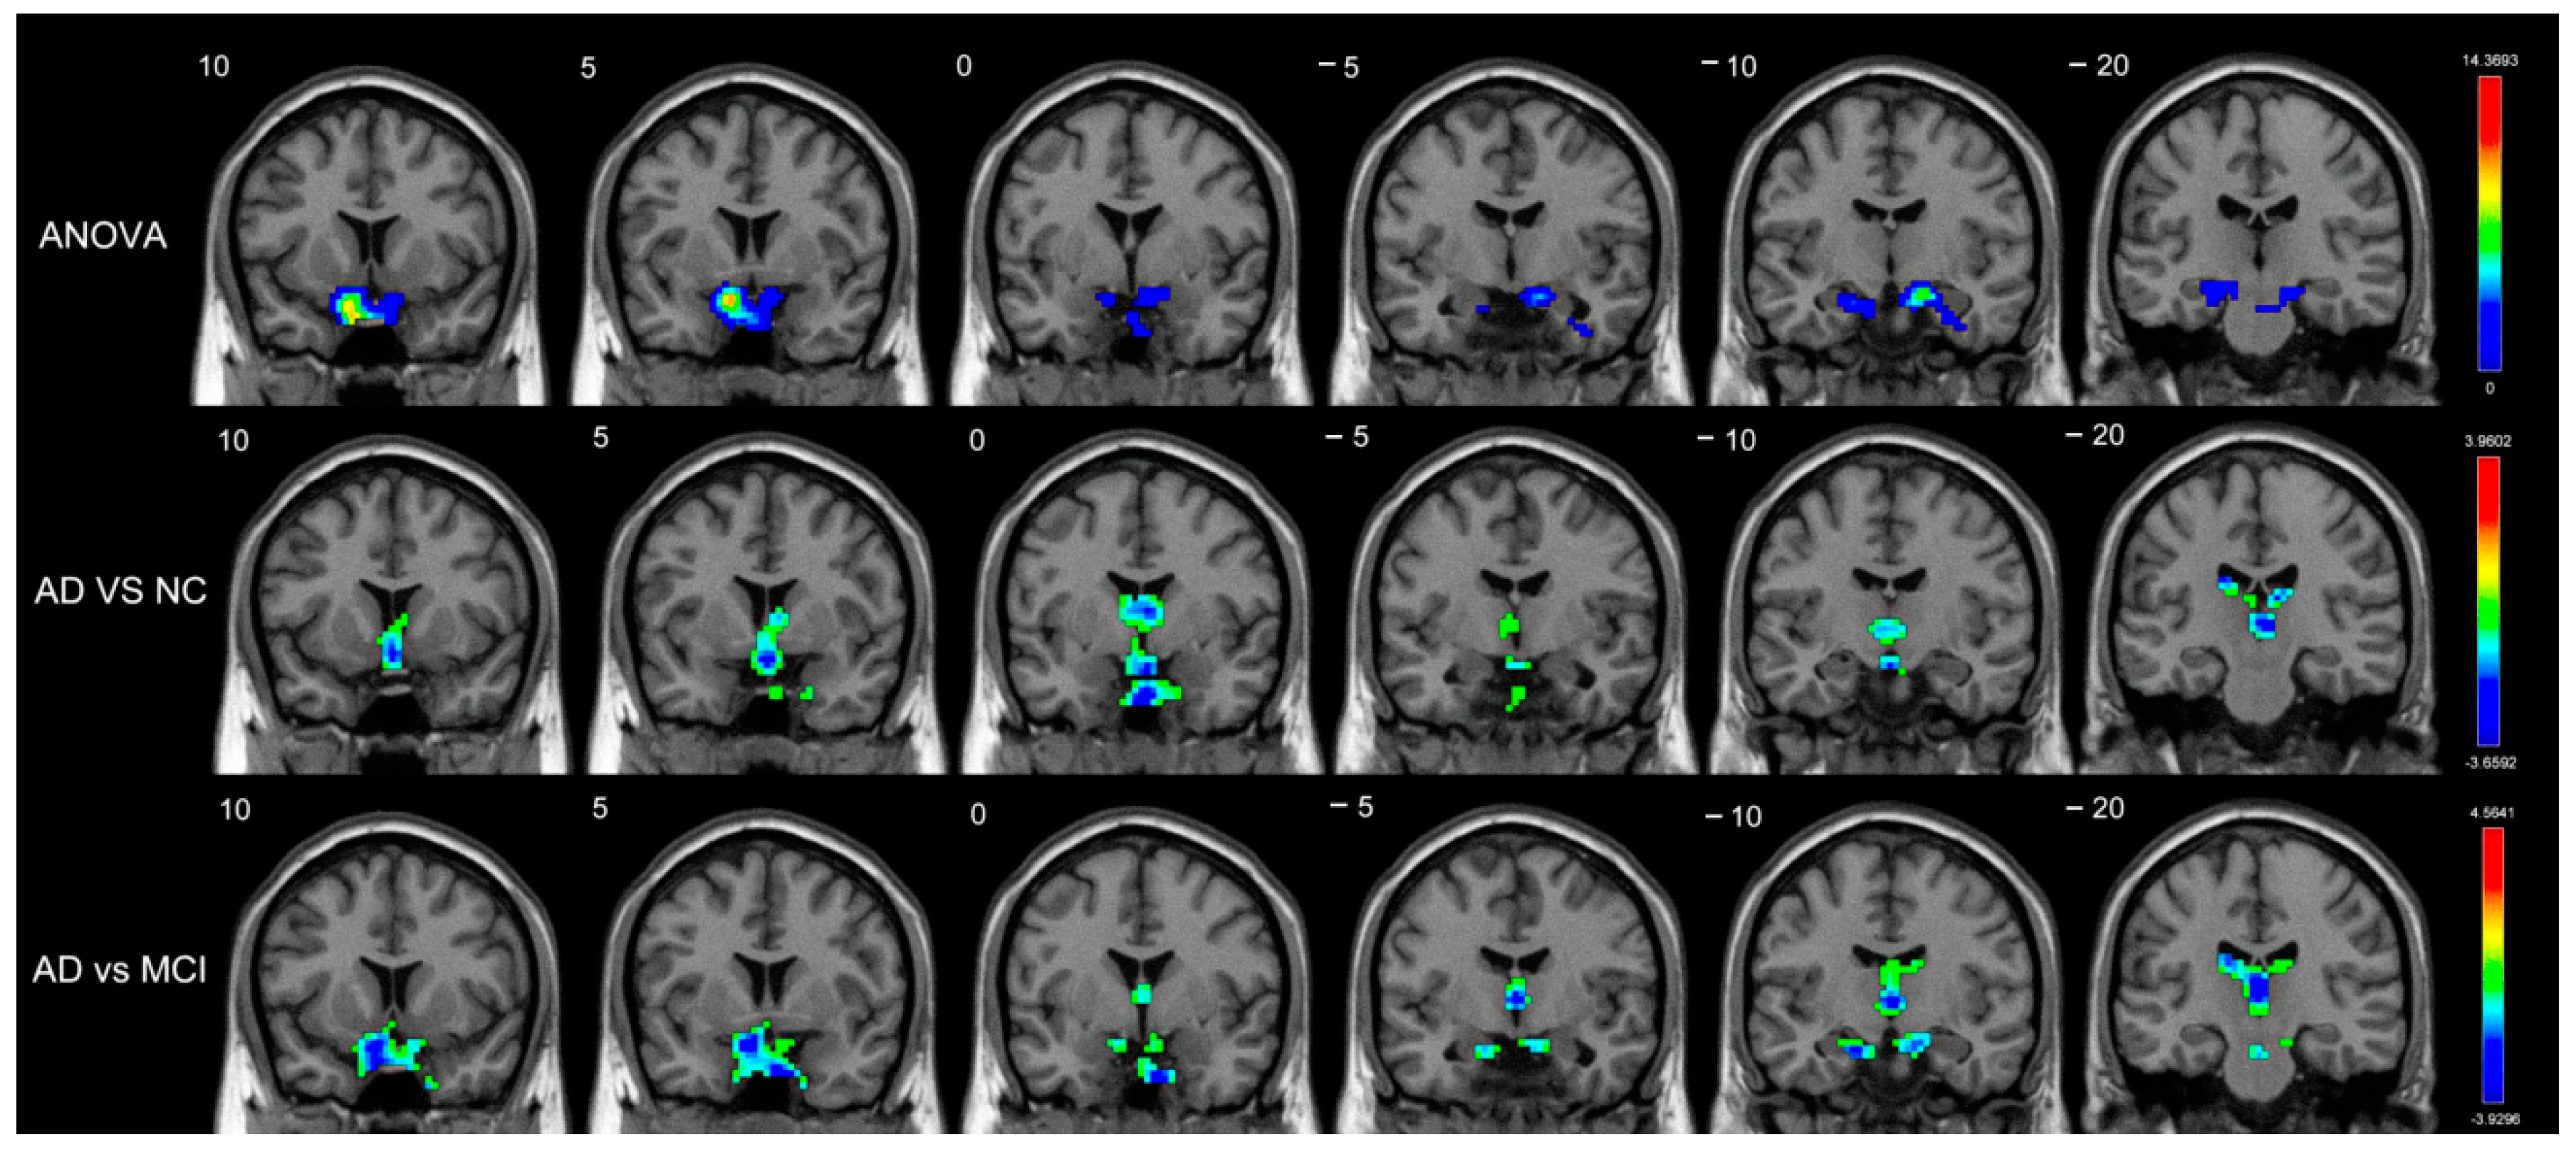

| ANOVA | |||||

| Short-range | Amygdala_R | BA34 | (18,0,−17) | 5.9018 | 3 |

| Long-range | Caudate_R | - | (18,−5,20) | 11.3438 | 66 |

| Caudate_L | - | (−16,−12,23) | 6.4713 | 43 | |

| Amygdala_R | BA34 | (19,1,−17) | 13.2933 | 32 | |

| Pallidum_R | BA48 | (19,0,−5) | 7.8705 | 14 | |

| Putamen_R | BA48 | (33,−9,0) | 6.1615 | 7 | |

| AD vs. NC | |||||

| Short-range | Caudate_L | - | (−7,1,11) | −2.9712 | 29 |

| Caudate_R | - | (9,5,7) | −2.8622 | 8 | |

| AD vs. MCI | |||||

| Short-range | Caudate_L | - | (−18,−21,23) | −3.2570 | 9 |

| Caudate_R | - | (16,−18,21) | −2.8545 | 4 | |

| Long-range | Caudate_L | - | (−15,14,18) | −3.7649 | 66 |

| Caudate_R | - | (17,6,23) | −3.7601 | 54 | |

| Amygdala_R | BA48 | (19,2,−11) | −3.6551 | 20 | |

| Pallidum_R | BA48 | (19,−3,−2) | −3.4747 | 9 |